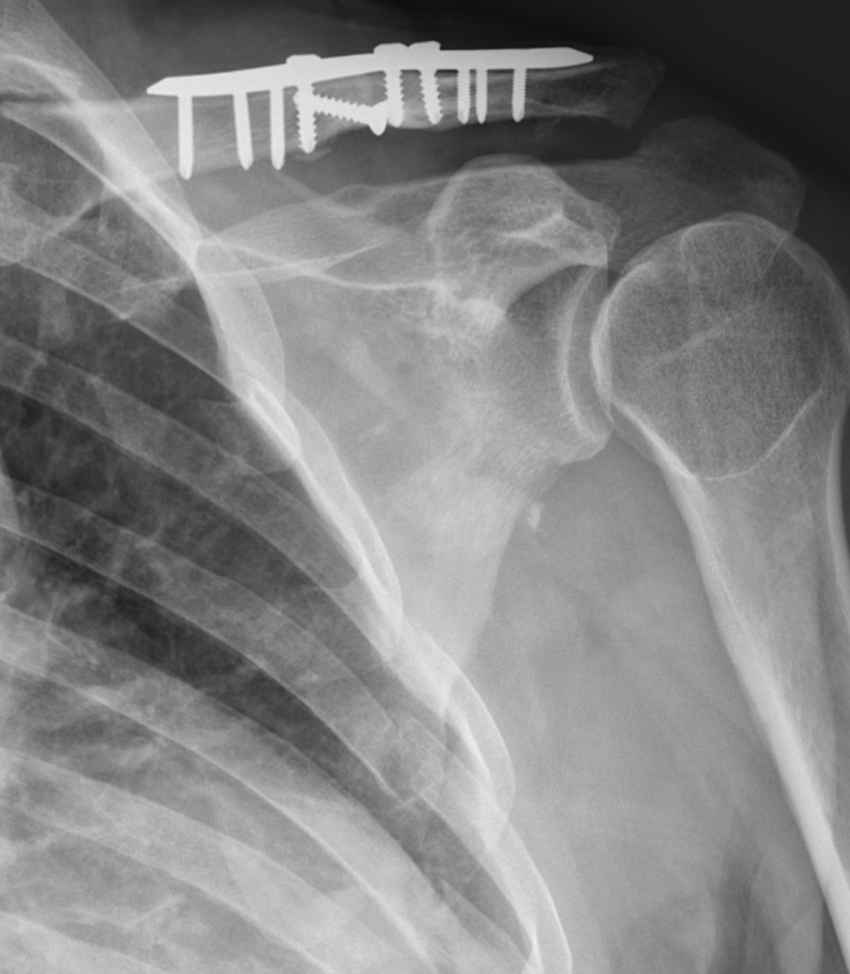

Clavicular osteosynthesis

During the operation, we will reposition the broken pieces of bone and stabilise them using a small metal plate and screws. This fixation allows the bone to heal in the correct position, helping to restore shoulder alignment, movement, and strength.